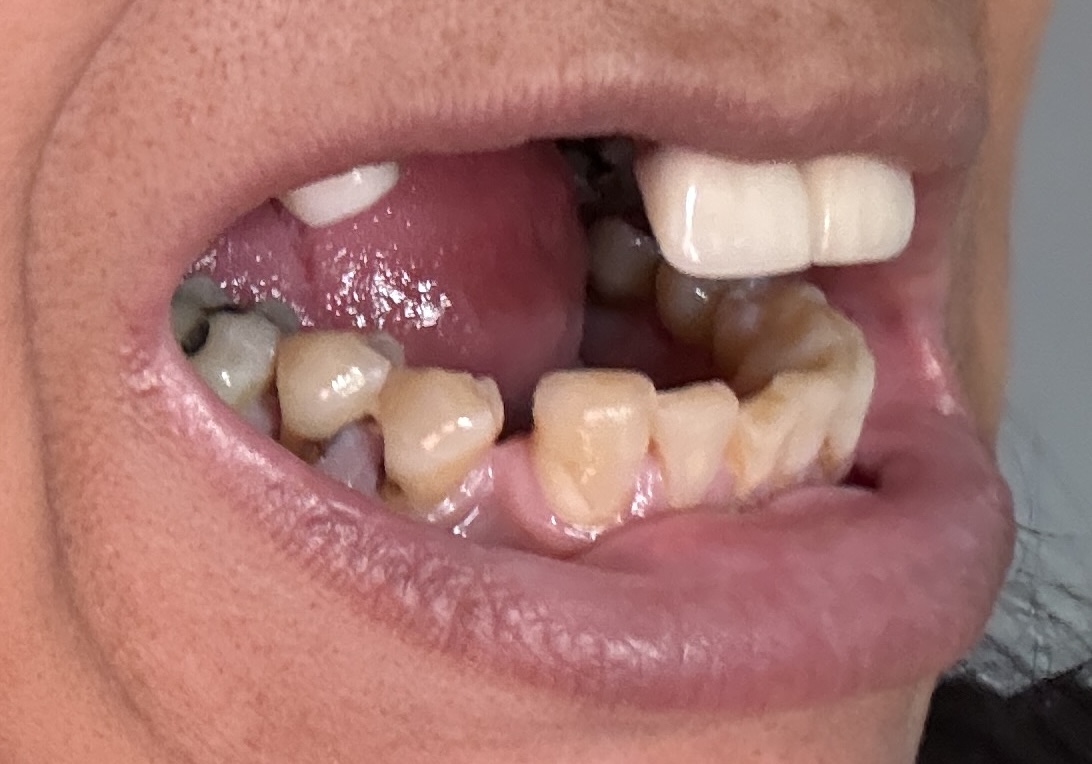

Dental Auction No. 11561: Several extractions and All-on-4 Top and bottom arches

12,13,14 have had root canals in past and now have quite a bit movement. 2-5 have all had root canals in past and now the crowns are breaking down.

Overall, all of my gums have receded and most of the bottom teeth are exposed w/ some roots and there are many cavities.